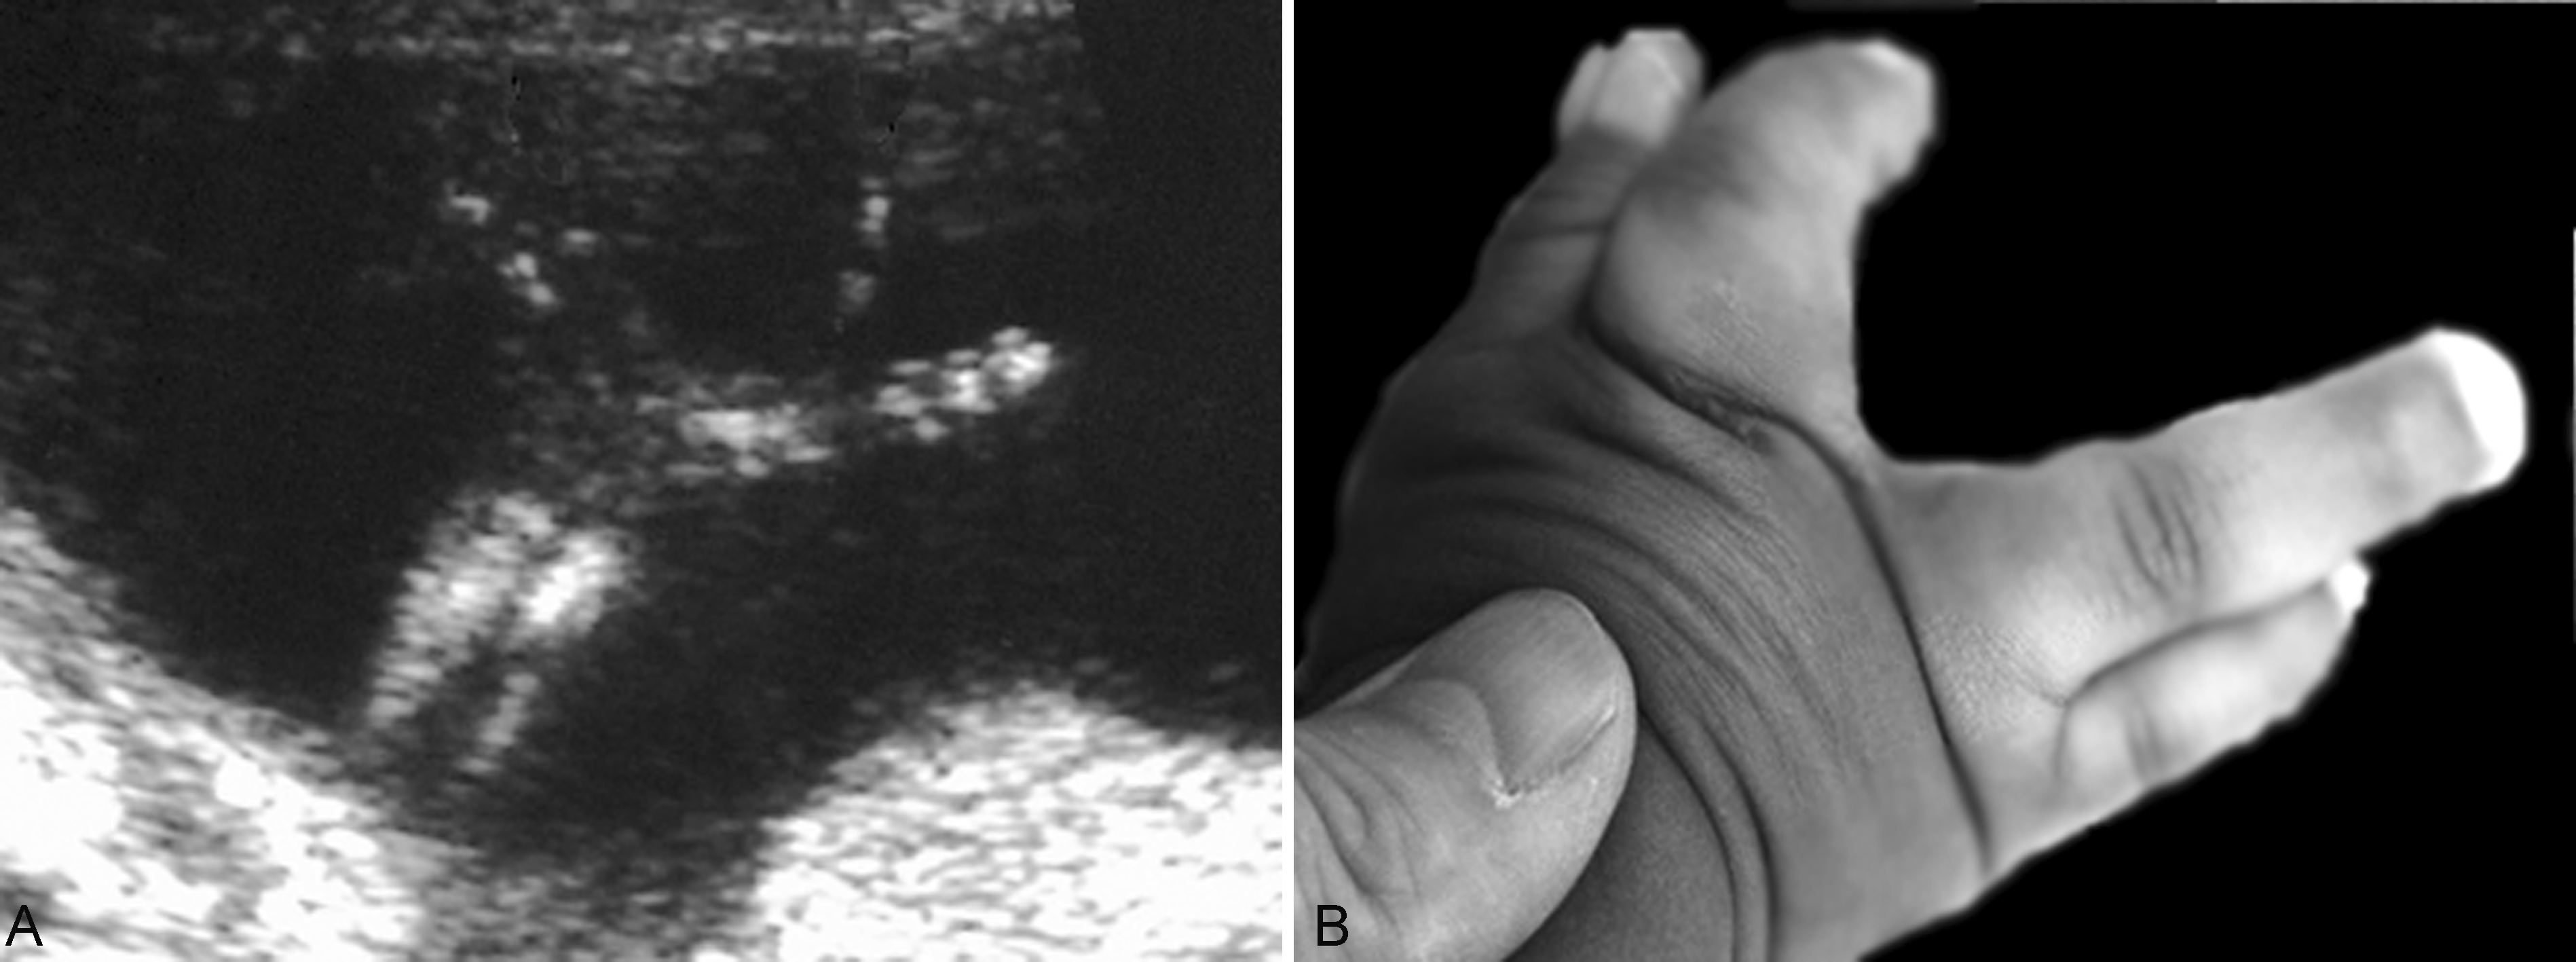

3.手和足的评估 手(足)的评估包括手(足)的大小、形态异常和多指(趾)、短指(趾)畸形等,如剪刀手(图5)、凉鞋足、多指(趾)、并指(趾)等,但已经公布的国内外超声检查规范中都没有把肢端掌(跖)骨和指(趾)骨的超声检查作为产前超声检查必须的内容。

图5胎儿剪刀手畸形:A:剪刀手声像图;B:出生后手部照片

由于肢端部具有灵活的运动功能,屈、伸、内收、外翻、旋转等灵活多变,超声显像检查时显示的一种位置并不一定由发育异常引起,也可能处于一种临时的运动状态。反复多次的检查可能显示诸如多指(趾)、并指(趾)、短指(趾)、马蹄内翻足等畸形(图6),三维超声显像检查有助于对畸形的显示和判断。多数需要出生后检查明确诊断。

图6胎儿足内翻畸形(B为出生后胎足照片)